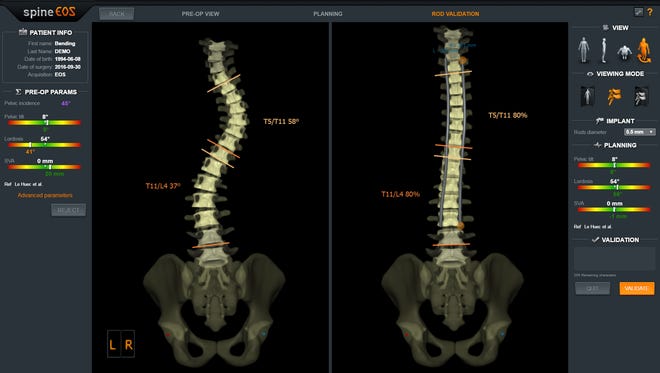

Whatsapp x WhatsApp Number Message phone x email x info@imagesradiologycom If you know, EOS is a low dose weight bearing XRay technology Images of the human body or the skeletal system can be produced in 2D or 3D form Contact us Home;The EOS Imaging System is a revolutionary advance in xray imaging Using Nobel Prizewinning technology, the ultralowdose system scans our patients in an upright, weightbearing position in seconds This allows the doctor to see the natural way that their joints interact with their musculoskeletal system, making it ideal for diagnosing

Eos x ray system-EOSedge EOSedge is a precise, low dose imaging system that delivers full body, highquality images covering the full set of musculoskeletal and orthopedic exams This next generation solution captures fully functional 2D/3D biplanar images in seconds, using a highresolution photoncounting detector for outstanding image quality for a broad range of patientsEOS imaging is a medical device company based in Paris, France, that designs, develops, and markets EOSedge and the EOS system, innovative, orthopedic medical imaging systems, associated with several orthopedic solutions along the patient care pathway – from diagnosis to postoperative treatments The EOS platform targets musculoskeletal disorders and orthopedic

The new EOS Xray system uses significantly lower radiation in the diagnosis of scoliosis Patients stand or sit inside the imaging system while it takes spAbstract Background EOS is a biplane Xray imaging system manufactured by EOS Imaging (formerly Biospace Med, Paris, France) It uses slotscanning technology to produce a highquality image with less irradiation than standard imaging techniques Objective To determine the clinical effectiveness and costeffectiveness of EOS twodimensional (2D)/threedimensional (3D) X The EOS™ Xray machine, based on a Nobel prizewinning invention in physics in the field of particle detection, is capable of a simultaneous capture of biplanar Xray images by slot scanning of the whole body in an upright, physiological loadbearing position, using ultralow radiation doses

EOS is highly efficient as this imaging system uses low does of radiation compared to the other MRIs It can give the physicians a better hand to preplan the treatment for the children which can bring out effective results An EOS scan can effectively show the child’s natural weight bearing posture and even allows us to see the interaction between joints and hips, spine and legs EOS Xrays produce highquality detailed images and expose patients to significantly lower doses of radiation than traditional Xrays “An EOS imaging system is important for kids with scoliosis because the radiation dose is about 1/7th of a normal Xray dose at the initial visit and much lower still for followup Xrays using the microdoseNo evidence was found on the impact of EOS on patients' pathways of care or ultimate health outcomes Radiation dose is considerably lower with EOS than CR or film Xray imaging, whereas image quality remains comparable or better with EOS Patient throughput is the major determinant of the costeffectiveness of EOS